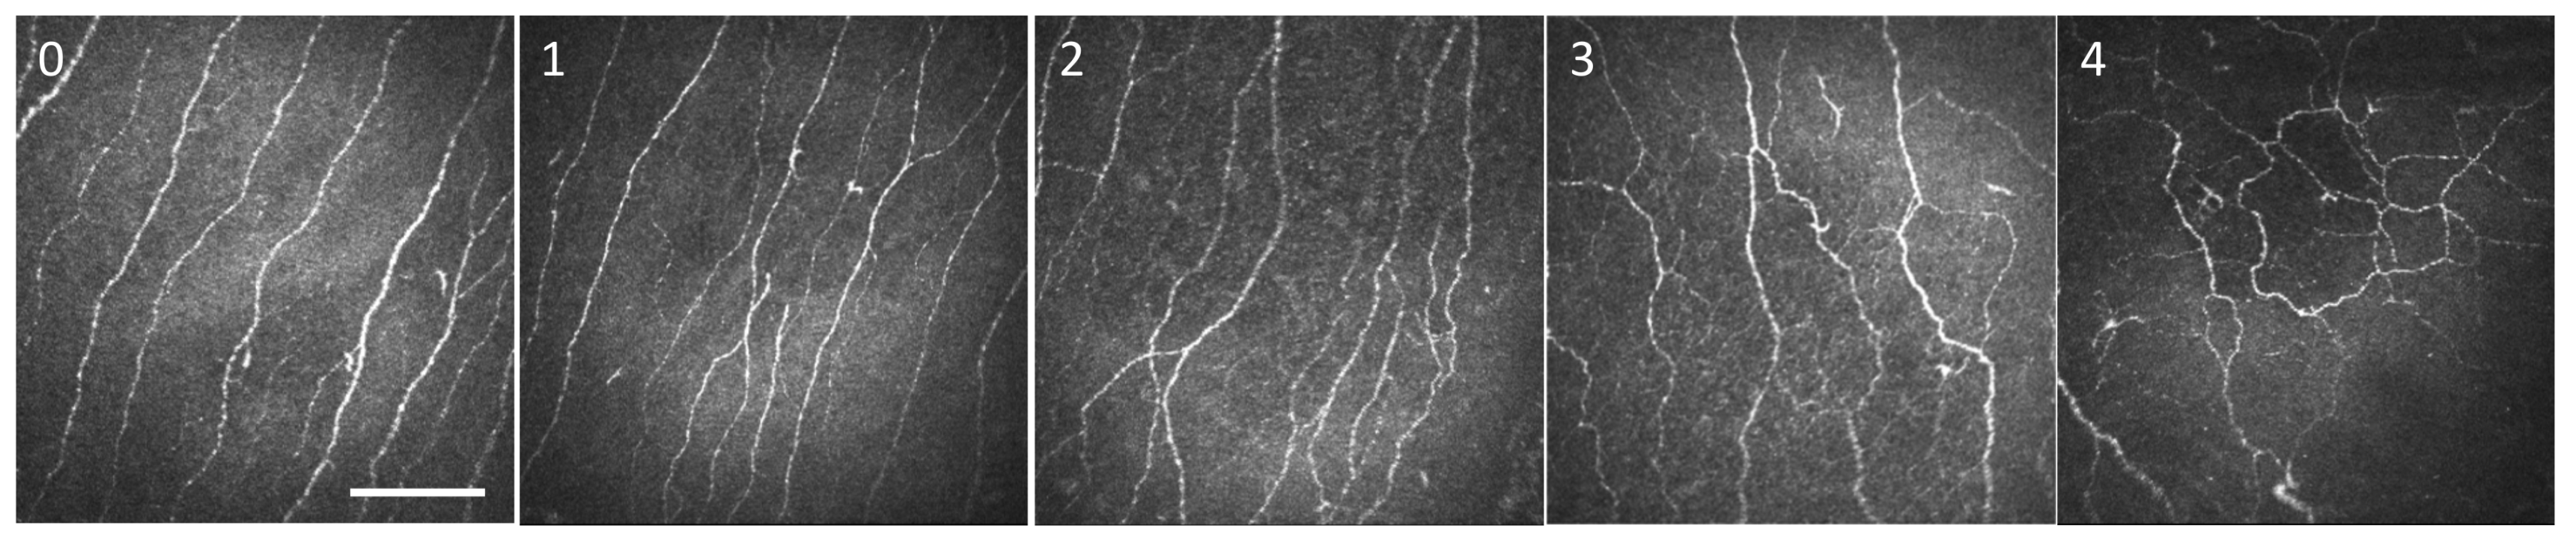

2.4. In Vivo Confocal Microscopy: Image Selection and Analysis

Image Selection and Analysis

3.5. IVCM Image Analysis

3.6. DED-Related NCP Patients Have Significant IVCM-Identified Corneal Nerve Alterations Compared with Healthy Controls

3.7. MGD-Related NCP Patients Had Higher Microneuromas Compared with Painless MGD and AIDE-Related NCP Patients

3.8. Higher Microneuroma Found in Painless DED Patients Compared with Healthy Controls

3.9. Structural Differences in Microneuromas between Painless MGD Patients and AIDE Patients

4. Discussion